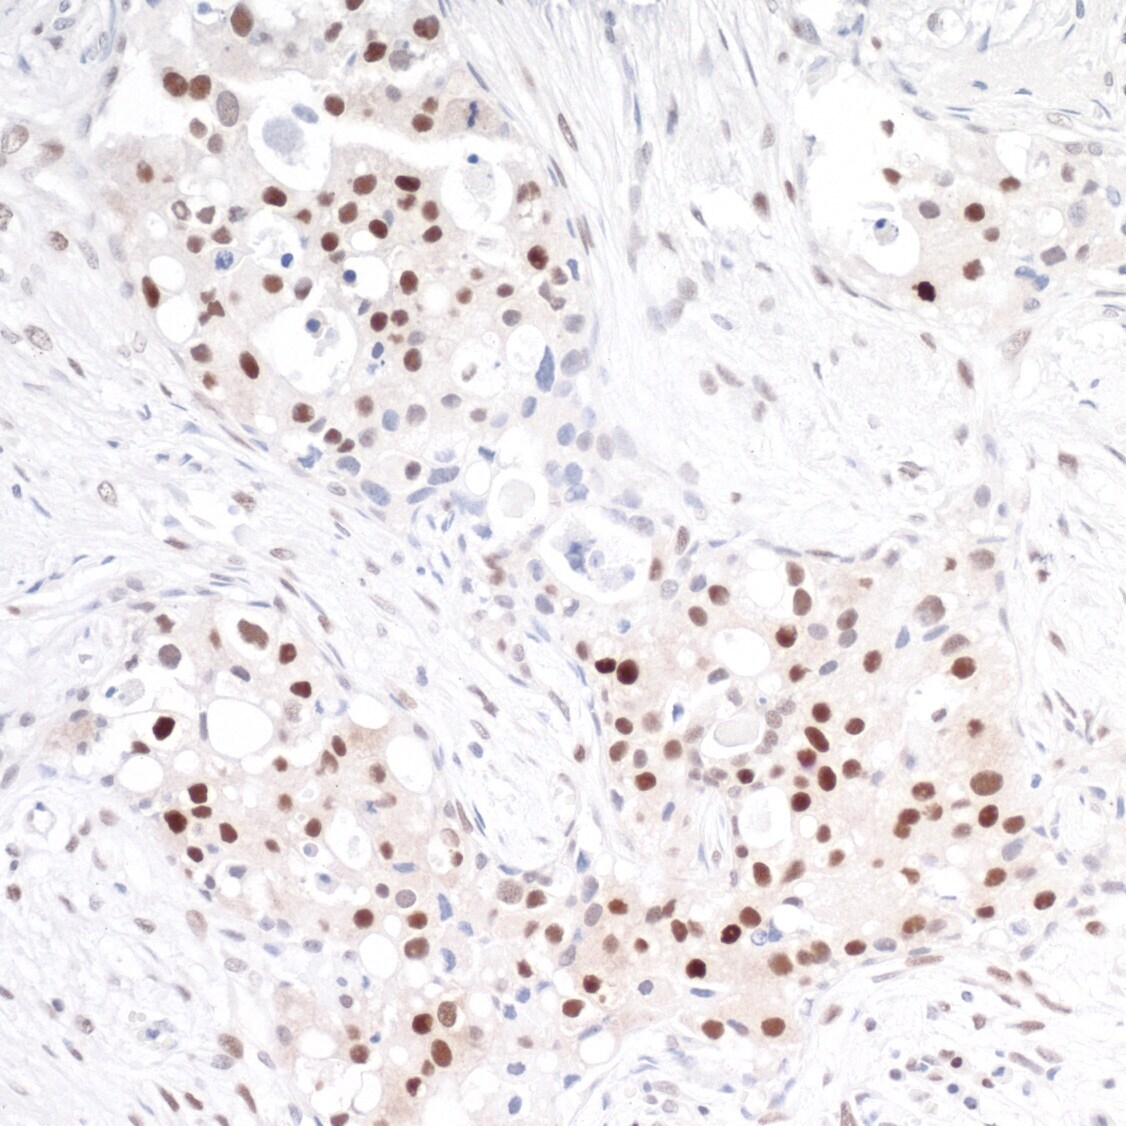

- Detection of human TRAF4 by immunohistochemistry. Sample: FFPE section of human lung cancer. Antibody: Affinity purified rabbit anti-TRAF4 (Cat. No. A302-841A Lot2) used at a dilution of 1:1,000 (1µg/ml). Detection: DAB.